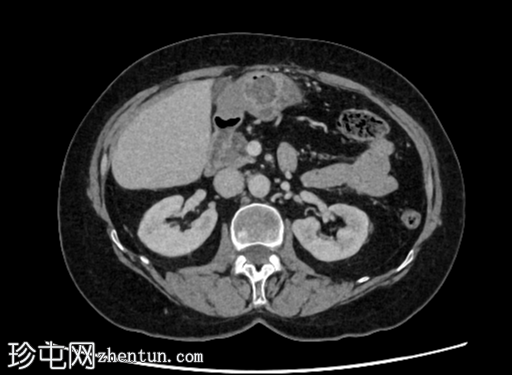

轴位

平扫

右肾后上极可见2.8 cm外生性强化病灶,提示肾细胞癌(RCC)。右肾静脉和下腔静脉通畅。未见明显局部淋巴结肿大。右肝叶可见高密度金属影。可见含脂肪的脐疝。